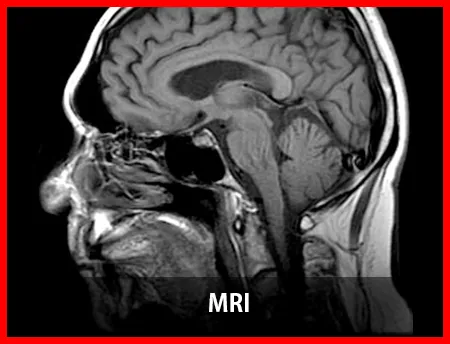

MRI는 고가의 의료 장비와 전문 인력이 필요한 검사다. 장비 도입 비용과 유지 비용, 검사 해석 과정이 검사비에 반영되는 구조다. 이로 인해 다른 영상 검사보다 비용이 높게 책정되는 경우가 많다.

뇌 MRI는 신경학적 증상 확인에 사용된다. 검사 범위와 촬영 방식에 따라 비용 차이가 발생할 수 있다.